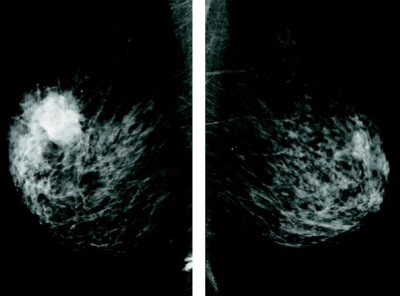

60 歳の女性。右乳房のしこりを主訴に来院した。胸部の触診で右乳房に径3cmの腫瘤を触知する。両側のマンモグラムを別に示す。

まず行う検査として適切なのはどれか。

e. 超音波ガイド下針生検

乳癌を疑った場合にまず行う検査である。